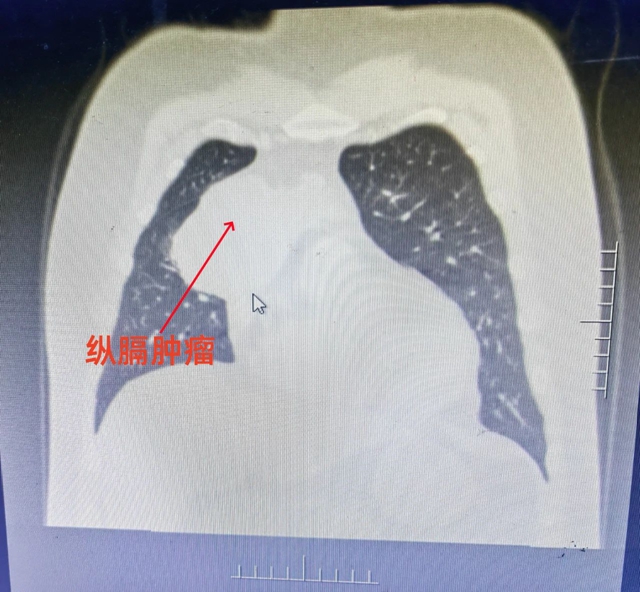

近日,杨先生突然出现右侧胸痛,于当地医院初诊后,遂至西南医科大学附属医院胸外科进一步就诊,诊断为纵隔肿瘤,经CT显示其肿瘤直径达12公分,为巨大纵隔肿瘤。

同时,因胸腔纵隔内位置特殊,生长在心脏主要血流通道——动、静主动脉表面,骑跨两侧胸腔,肿瘤又达12公分之大,手术操作稍有闪失,便可能引发心脏大血管大出血,导致患者生命危险,进一步加大了手术难度。再加上患者本身又患有高血压,这也是外科手术发生出血风险的高危因素之一。